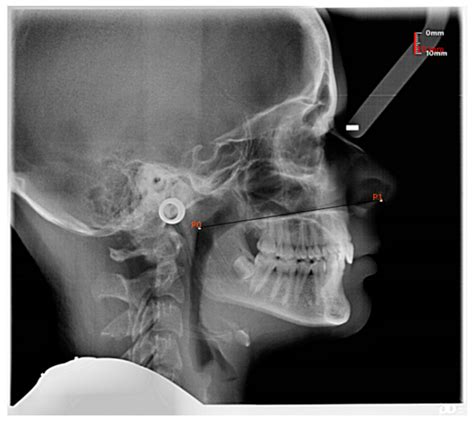

• Imaging Tests: X-rays or CT scans may be ordered to assess the size and condition of the adenoids.